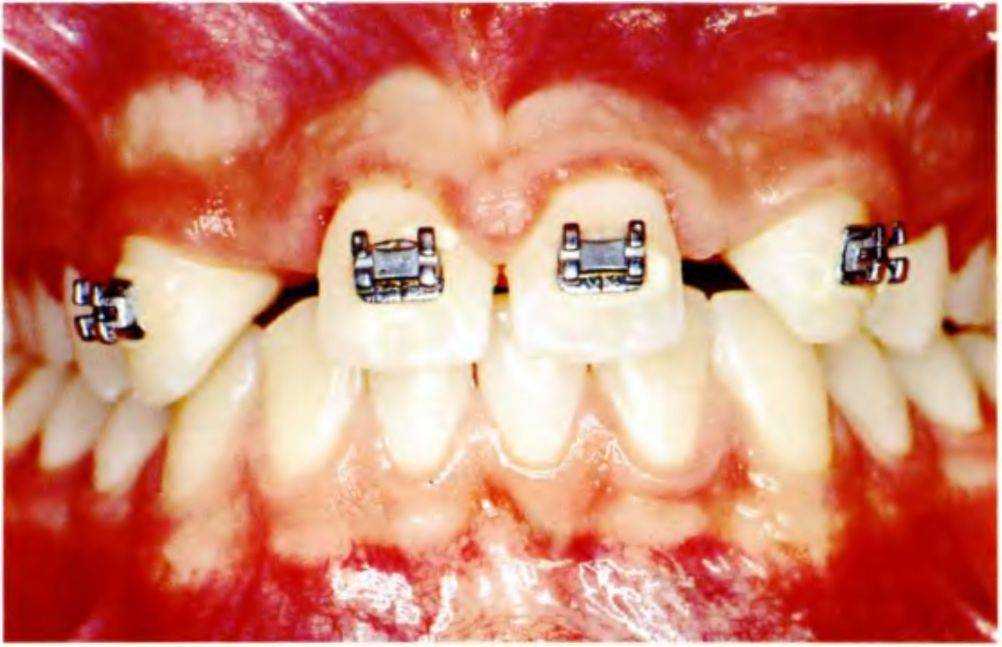

Рис. 5-3d. Клиническая картина после увеличения пространства ортодонтическими методами

Планируется перемещение зубов латерально для создания пространства для установки имплантатов и последующего протезирования (рис. с 5-За по 5-Зе).